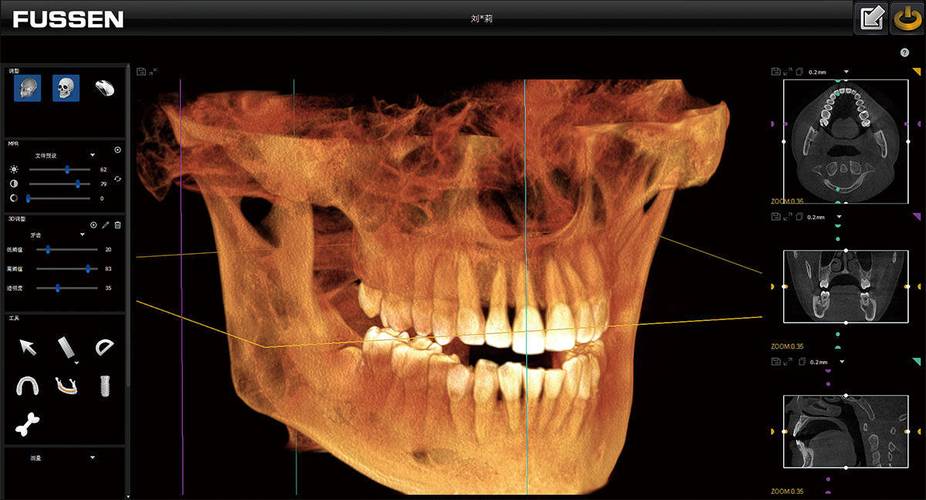

口腔CT(CBCT)——口腔的“3D立体导航”

- 一句话概括: 它是口腔领域的“CT扫描”,能生成我们口腔颌面部高精度的三维立体图像,就像一个“立体导航系统”。

- 工作原理: X射线围绕患者头部做360°旋转,探测器采集数据后,通过计算机软件重建出三维的、可任意旋转、切割、放大的数字模型。

- 它能告诉我们什么?(优点)

- 三维立体: 清晰展示牙齿、颌骨、神经、血管的立体结构和空间关系,无重叠干扰。

- 精度极高: 可以精确测量骨量、牙根长度、角度,分辨出0.1毫米级别的细微病变。

- 信息全面: 能清晰显示牙槽骨的厚度、高度、密度,以及重要的解剖结构,如下牙槽神经管、上颌窦等。